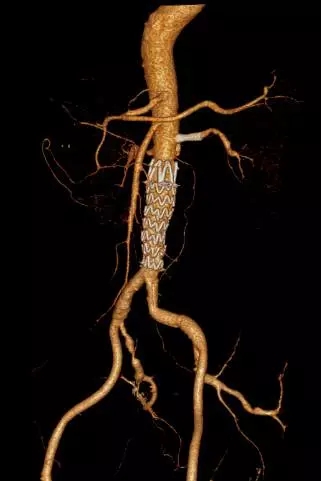

在麻醉科及手术室的配合和支持下,手术过程非常顺利,经过右侧股动脉小切口,成功将1枚主动脉覆膜支架植入病变部位,同期将左侧肾动脉植入1枚自膨支架,成功解除肾动脉狭窄,整个手术过程仅耗时2小时,术后患者即清醒返回病房。施敏护士长高度重视,安排骨干护士全程监护患者病情,每日翻身拍背、排痰、气压治疗,积极预防肺部感染、压疮、下肢深静脉血栓等并发症。术后2周患者康复出院,复查CTA(图3),支架位置良好,夹层被完全隔绝,无内漏发生,肾动脉支架通畅,狭窄解除。孙师傅和家属对王兵教授高超的技术和施敏护士长带领的护理团队的精心照料赞不绝口。

图3